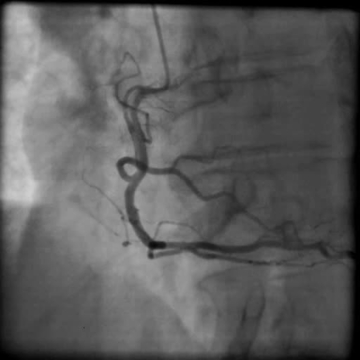

Koronarografické vyšetření provedené cestou stacionáře prokázalo hemodynamicky nevýznamné stenózy koronárních tepen – 30% stenózu RIA II a 50% stenózu odstupu RD1 (video 3). Pro nález koronární aterosklerózy byla do terapie přidána kyselina acetylsalicylová 100 mg/d.

Video 3. Selektivní koronarografie. 3A – zobrazení levé koronární tepny, 3B – zobrazení pravé koronární tepny. Nález bez hemodynamicky významných stenóz